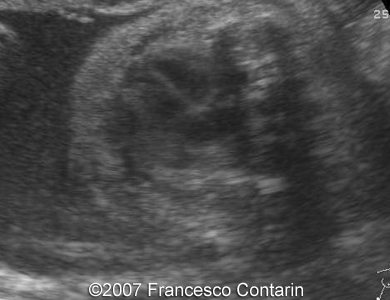

Images 13, 14. 29th week of pregnancy -  sagittal cranial plane - normal (left); and axial plane through the posterior fossa of the skull - normal cerebellum with transcerebellar diameter concordant with gestational age (right).

13

14